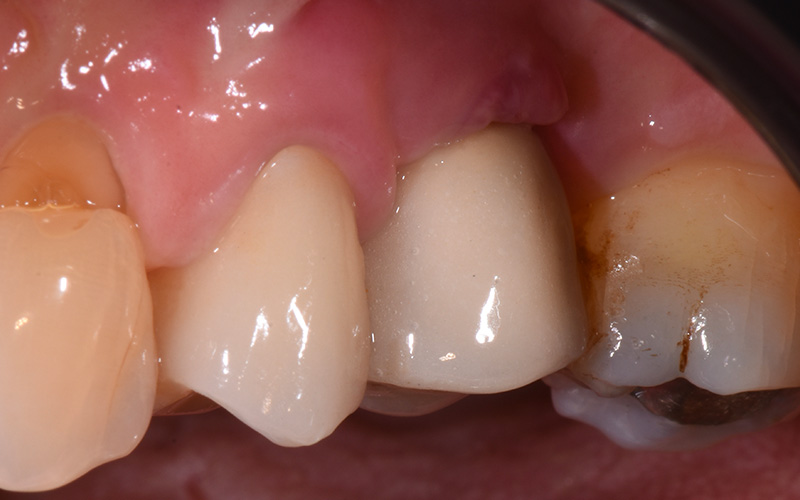

Dettaglio dell'elemento interessato da perimplantite

Fig. 2 - Dettaglio dell'elemento interessato da peri-implantite con evidente situazione clinica patologica.